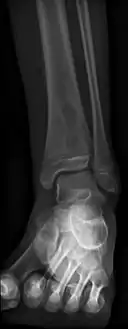

Oval, elliptical, or serpentine radiolucency usually greater than 1 cm surrounded by a heavily reactive sclerosis, granulation tissue, and a nidus often less than 1 cm. The margins often appear scalloped on radiograph. Brodie's abscess is best visualized using computed tomography (CT) scan. Associated atrophy of soft tissue near the site of infection and shortening of the affected bone. Osteoblastoma may be a classic sign for Brodie's abscess.

- Periostial reaction along the medial cortex indicates an aggressive lesion. Neoplasm such as Ewing sarcoma and osteomyelitis could both have this plain radiographic appearance. Staphylococcus was recovered at surgery.